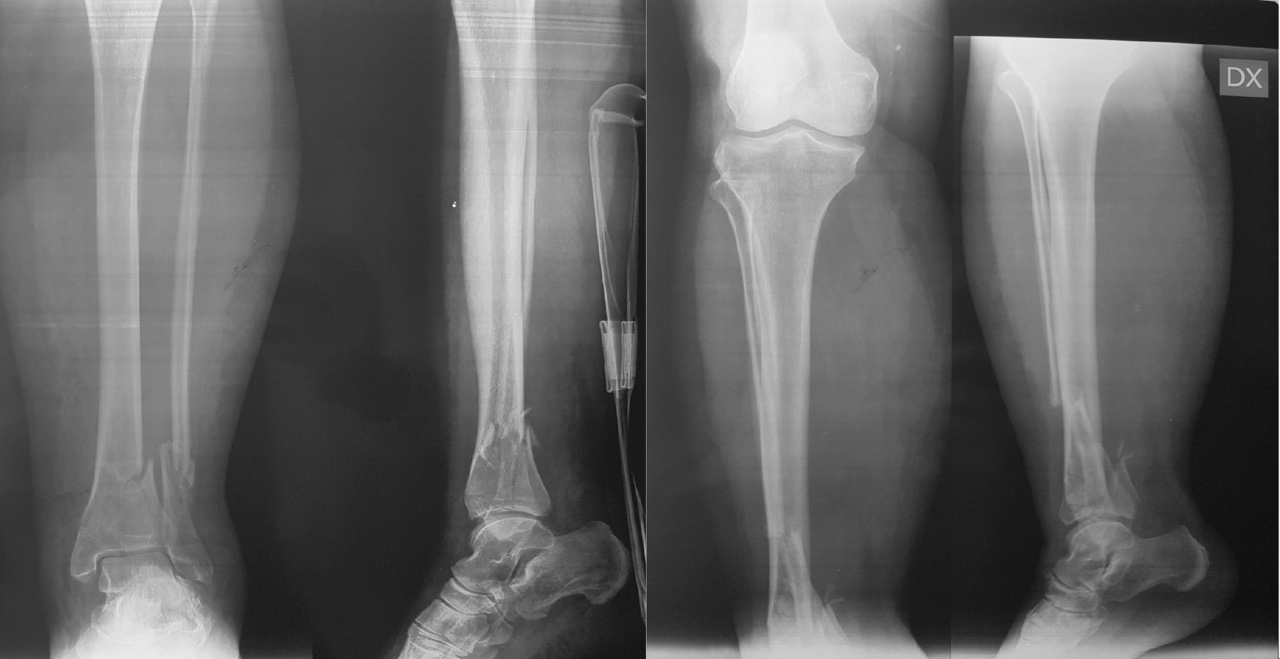

Il trattamento delle fratture di pilone tibiale deve essere accuratamente pianificato, le vie di accesso sono molteplici, il posizionamento del paziente può variare e la scelta dei mezzi di sintesi è particolarmente vasta. Per poter garantire il miglior trattamento al paziente è imprescindibile un accurato studio radiografico della frattura. La diagnosi può essere definita grazie alle classiche radiografie eseguite nelle tre proiezioni (AP, LL e AP obliqua) (Fig. 1).

). Questo esame di primo livello consente la classificazione della frattura secondo il sistema proposto da Ruedi e Allgower in tre stadi a seconda del numero dei frammenti e della scomposizione. Il sistema alfanumerico proposto dall’AO invece, classifica le fratture di pilone tibiale come 43B e 43C, cioè le fratture di tibia (4) distale (3) parzialmente (B) o completamente (C) articolari. La diagnosi eseguita tramite radiografia ci permette di passare alla prima fase del trattamento, cioè il posizionamento di un fissatore esterno temporaneo in distrazione associato o meno alla sintesi definitiva del perone. Una volta eseguita questa prima fase il paziente può essere sottoposto all’imaging di secondo livello con TC secondo il protocollo “Span & Scan”. La distrazione della tibiotarsica attraverso il fissatore esterno ci permette infatti, grazie a un meccanismo di ligamentotassi, un parziale riallineamento dei frammenti di frattura e di conseguenza un esame più accurato. Nel 2013 Cole et al hanno pubblicato un lavoro in cui, studiando nel dettaglio le scansioni assiali delle TC di 38 fratture di pilone tibiale, hanno potuto dimostrare la presenza di pattern più o meno comuni a tutti i pazienti 4. Il 100% delle fratture infatti aveva una rima che coinvolgeva la superficie articolare tibio-peroneale e da questa si dipartivano due linee di frattura (creando un pattern a Y) verso le porzioni anteriori e posteriori del malleolo mediale (Fig. 2).

Sono quindi di frequente riscontro tre macro-frammenti che possono essere definiti principali: un frammento mediale, uno antero-laterale e uno postero-laterale. La comminuzione è stata dimostrata nel 95% dei casi con presenza frequente di almeno un frammento impattato.